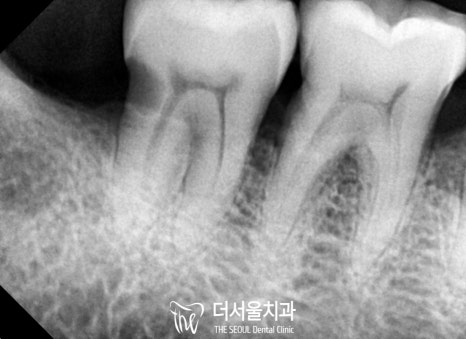

2020.09 초진

보시다시피 하악 전치부의 문제들이 심각했습니다.

그러나 이쪽에는 또 다른 문제가 있었는데요.

심한 치주 질환으로 공간적으로 뼈가 너무 없었습니다.

즉, 픽스처를 심기에는 어려움이 있다는 뜻이죠.